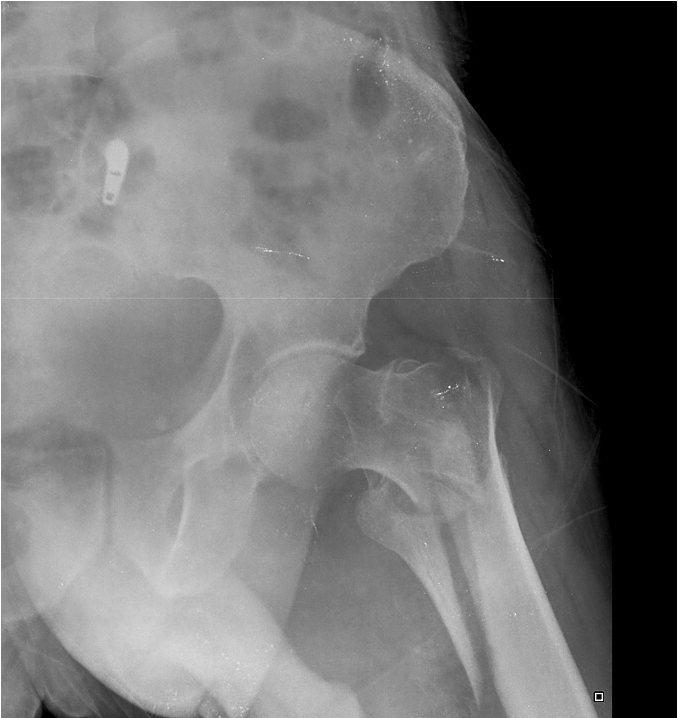

65 year old male:

fall onto left side while getting out of bed

AP radiograph of the hip

Prior DXR (bone density) scan showed marked osteoporosis

(extracapsular classification)

radiolucent intertrochanteric fracture of the left proximal femur

or

radiolucent oblique fracture through the greater trochanter and neck of the femur on the left side